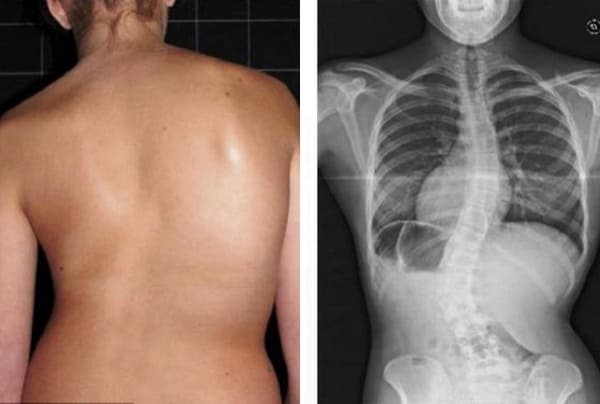

Todas as articulações requerem atenção, mas a coluna vertebral é prioritária. Preste atenção a ela antes que mudanças irreversíveis comecem a ocorrer. Eis o que espera àqueles que não prestaram atenção aos sinais do seu corpo: hérnia, deslocamento das vértebras, deformação da coluna vertebral, curvatura das costas, perda total da mobilidade. Não espere até que até mesmo um movimento simples se torne uma tortura!

Veja estas fotos. É isto que aconteceu com todos aqueles que ignoraram os sintomas. Hoje, estas pessoas estão completamente sem esperança e muitas delas não têm a quem recorrer para pedir ajuda. É mesmo isto que quer para a sua vida?

Mulher de 52 anos. Deslocamento e deformação acentuada do disco intervertebral, compressão do nervo e lesão da medula espinhal.

«Corcunda de viúva» — deformação da coluna vertebral e dor crónica e lancinante, que se intensifica a cada dia.

Hérnia do disco intervertebral, compressão do nervo, perda de sensibilidade e paralisia parcial das pernas.